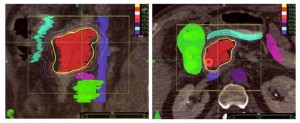

Τα παραδοσιακά συστήματα ακτινοθεραπείας στοχεύουν στη βλάβη από έναν σχετικά μικρό αριθμό σταθερών θέσεων. Αντίθετα, στην ρομποτική ακτινοχειρουργική με CyberKnife® επιλέγονται από το σύστημα εκατοντάδες γωνίες ακτινοβόλησης, που επιλέγονται ανάμεσα σε μερικές χιλιάδες θέσεις που υποστηρίζει το σύστημα. Έτσι έχουμε δυνατότητα να δώσουμε μεγάλες δόσεις θεραπείας στο στόχο στο πάγκρεας, επιβαρύνοντας ελάχιστα τους γύρω φυσιολογικούς ιστούς.

Τα παραδοσιακά συστήματα ακτινοθεραπείας στοχεύουν στη βλάβη από έναν σχετικά μικρό αριθμό σταθερών θέσεων. Αντίθετα, στην ρομποτική ακτινοχειρουργική με CyberKnife® επιλέγονται από το σύστημα εκατοντάδες γωνίες ακτινοβόλησης, που επιλέγονται ανάμεσα σε μερικές χιλιάδες θέσεις που υποστηρίζει το σύστημα. Έτσι έχουμε δυνατότητα να δώσουμε μεγάλες δόσεις θεραπείας στο στόχο στο πάγκρεας, επιβαρύνοντας ελάχιστα τους γύρω φυσιολογικούς ιστούς.